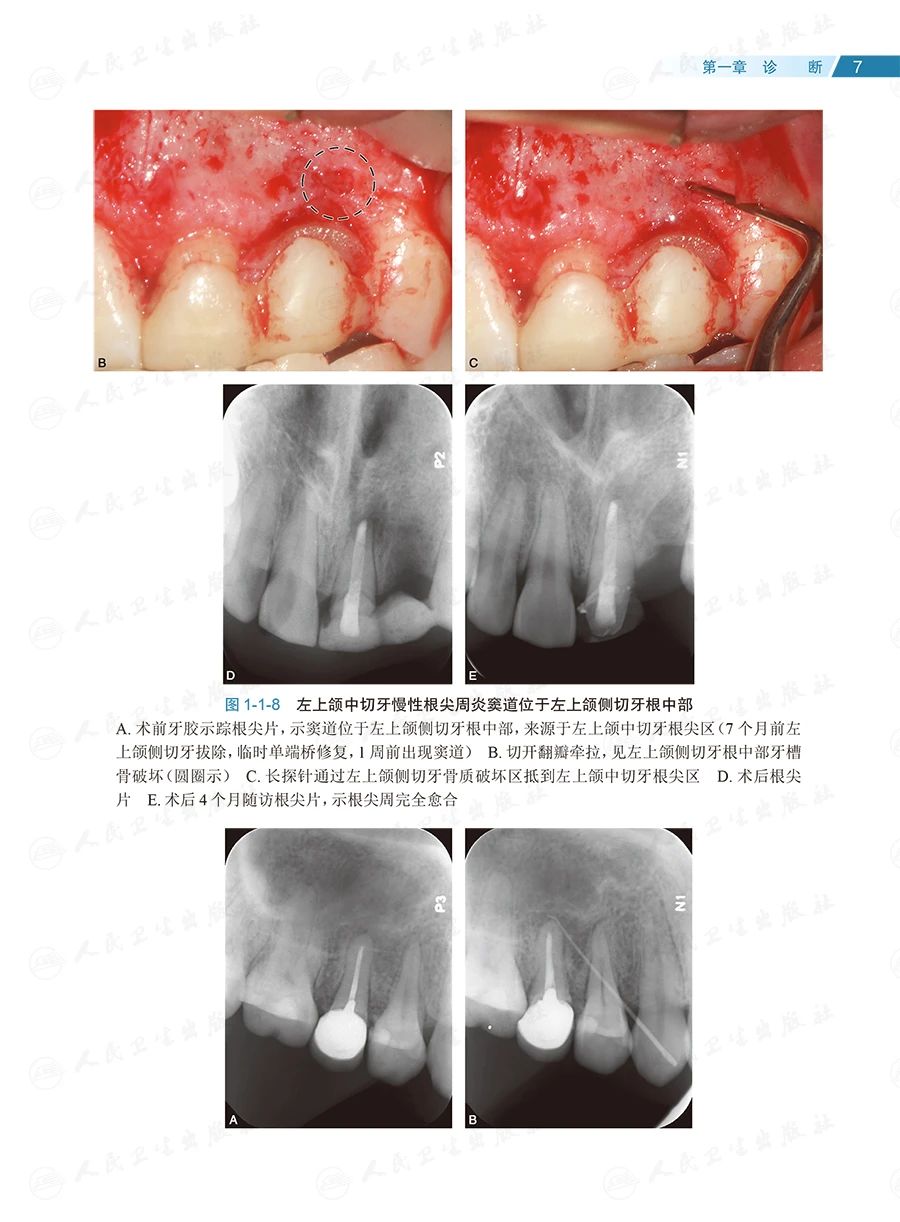

全书共133个临床病例、约1400幅照片,内容全面、图文并茂、形象直观。按照诊断、确定治疗方案和治疗的顺序,全书分为六章:第一章为诊断,主要讨论根尖周透射影、根裂的诊断和鉴别诊断;第二章为治疗方案选择,重点探讨非手术和手术(再)治疗方案的选择;第三章为在体手术治疗,即显微根尖外科,讨论特定牙位和牙根的手术,以及一些复杂疑难牙髓病、根尖周病的手术治疗;第四章为离体手术治疗,即显微意向再植术,全面讨论其适应证;第五章为多学科合作,包括牙髓源性上颌窦炎、联合应用引导性组织再生术(guided tissue regeneration,GTR)、自体牙移植术中的应用;第六章为全文总结,系统阐明牙髓病、根尖周病治疗的整体策略。